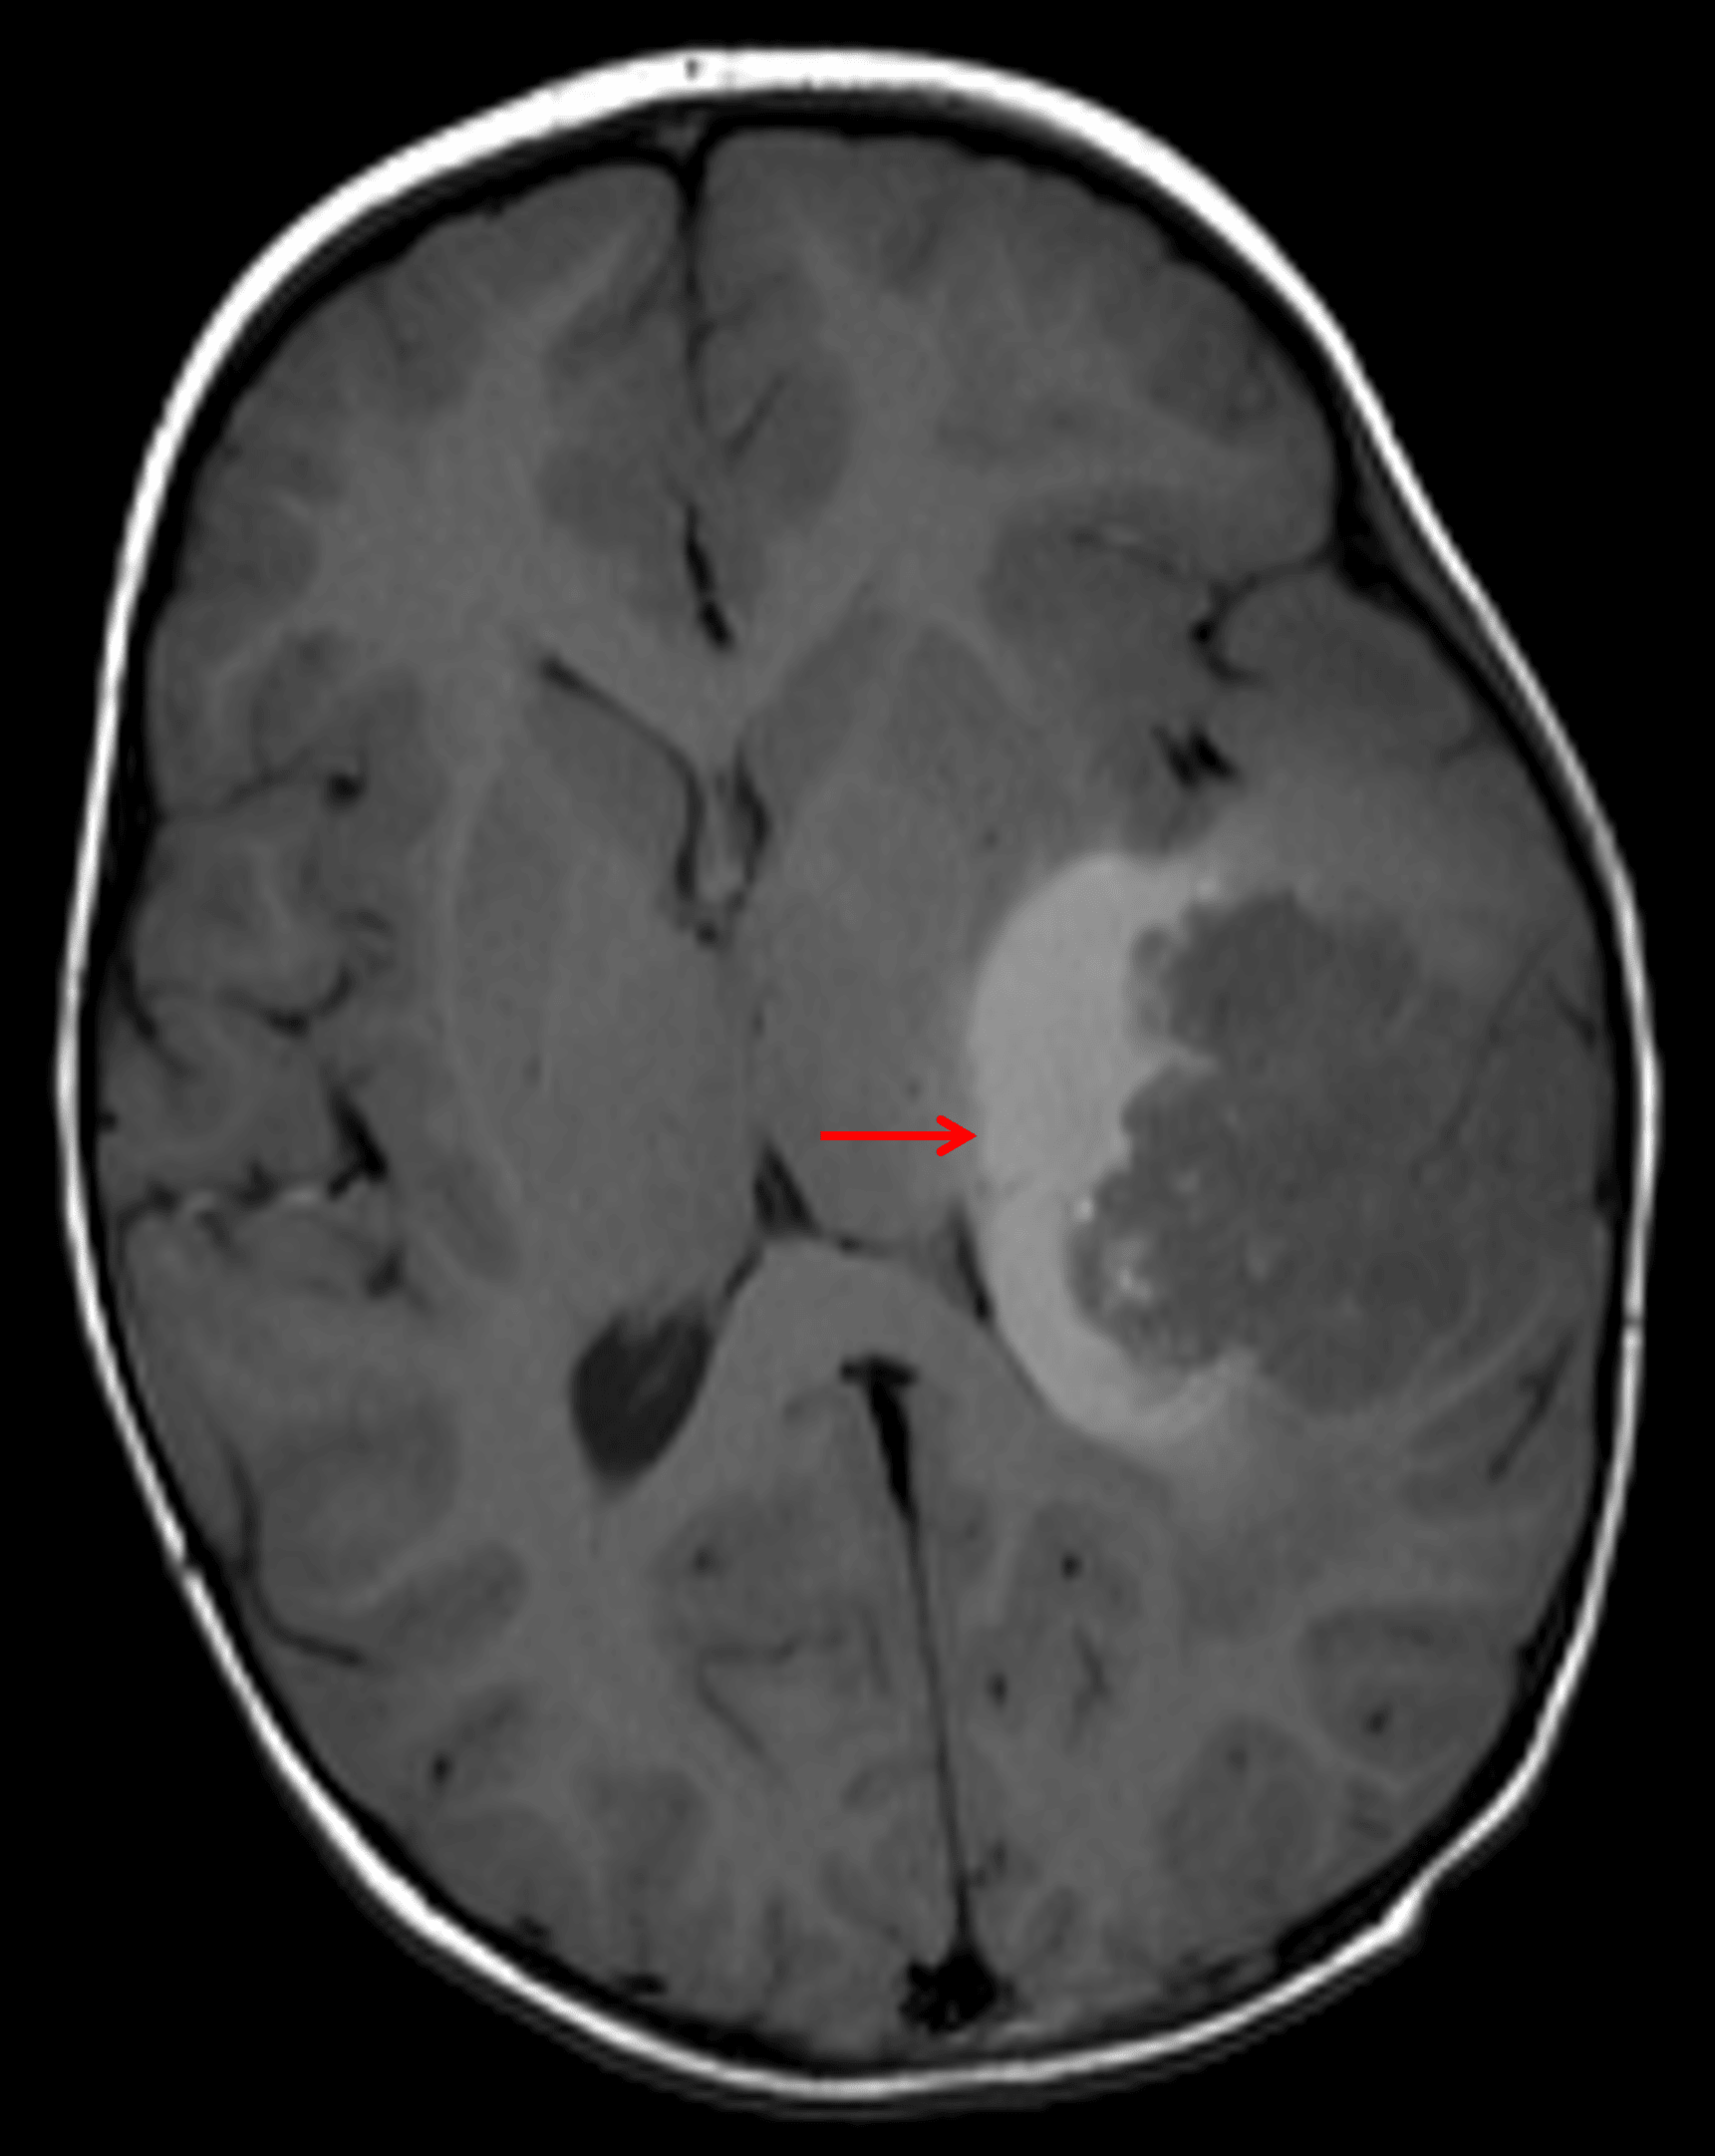

- Areas of intrinsic T1 signal hyperintensity, particularly along the deep margin of the mass

Area of T1 signal hyperintensity along the deep margin of the tumor (red arrow), likely representing tumor-related hemorrhage.